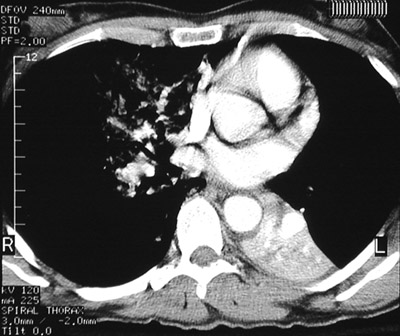

| These views above amd below from a chest CT scan reveal an aspiration pneumonia involving the right middle lobe. Note the ground glass opacifications and the bronchial hypodense material. In the view below is an area of left lower lobe consolidation from a prior aspiration followed by pneumonia. |